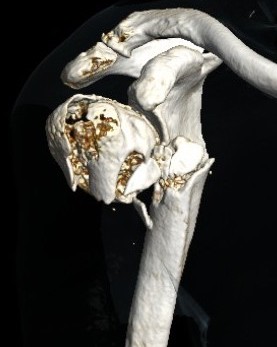

Severe comminuted proximal humerus fractures

100% displaced / off ended

Fracture - dislocations

- comminuted, 3 or 4 part

- head spltting fracture

- off ended / 100% displaced

Unreconstructable fracture - 4 part, comminuted, head spltting fracture